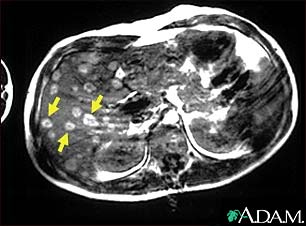

Melanoma of the liver - MRI scan

This upper abdominal MRI scan shows multiple tumors in the liver which have spread (metastasized) from a malignant melanoma in an arm or leg. Note the light circular areas throughout the liver (seen mostly on the left side of the screen).